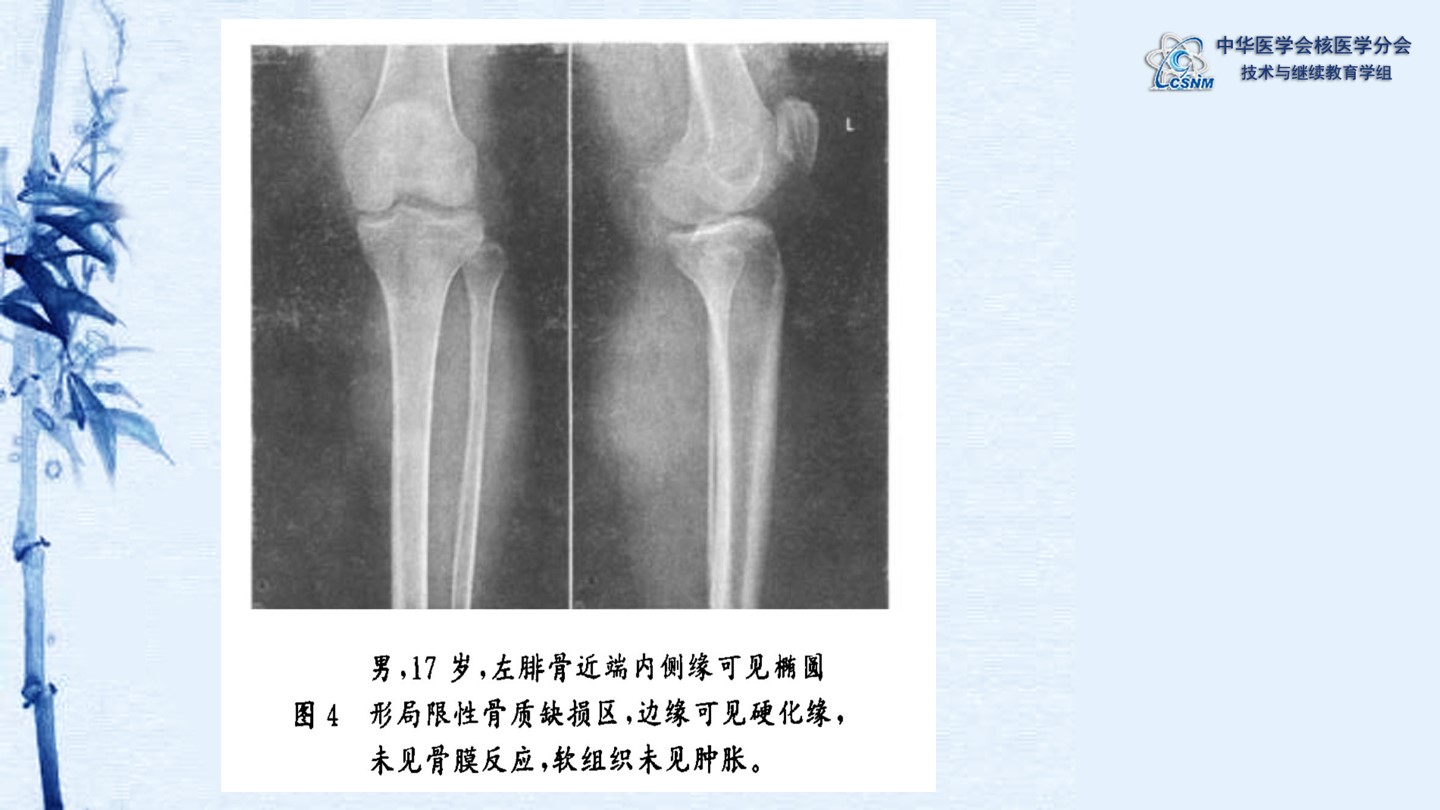

【CSNM继教学组】讲座E29 肖茜 常见良性骨肿瘤的SPECTCT表现